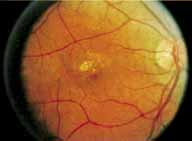

During the early stage of the dystrophy, when patients demonstrate a slight-to-moderate decrease in visual acuity and minimal color defects, there are minor or no visible fundus abnormalities. At most, the foveal reflex may be absent and there may be some increased granularity of the retinal pigment epithelium in the macula. Later, there is a decrease of visual acuity to the 20/400 range, oval atrophy of the macular retinal pigment epithelium (“beaten bronze” atrophy), and associated choroidal atrophy (Fig. 3). A characteristic bull's-eye maculopathy, similar to that seen in patients with chloroquine retinopathy, may also be seen.90 Photophobia, occasional nyctalopia, incomplete-to-complete color defects, and a central scotoma are often present. The symmetry of the process in both eyes is remarkable.

|